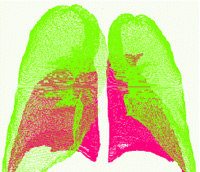

- 持续项目旨在开发自动或半自动方法定位并概述2D和3D数据解剖结构包括X射线计算断层扫描和磁共振图像我们的工作侧重于胸部结构, 特别是肺、肋骨、气管、肺裂变、肺结核和血管脉冲裂度介于肺叶间分片法基于迭代曲线增长过程 适应性权重本地图像信息 和先入之知分解法